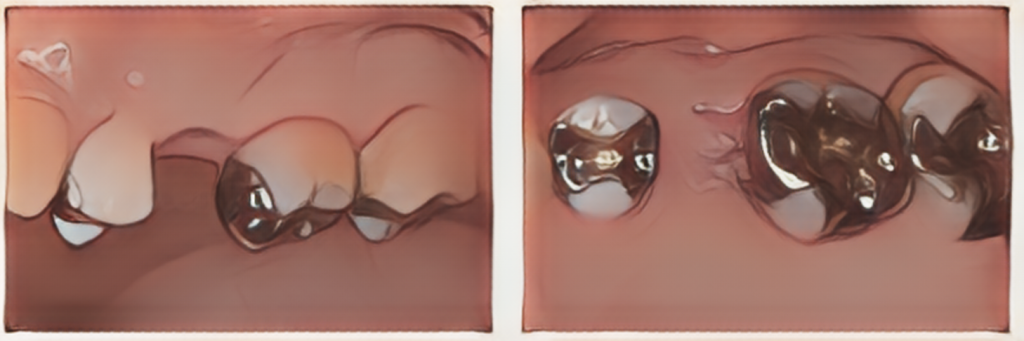

プロビジョナルレストレーションと言われる治療用義歯を装着し、機能性や清掃性の評価を行いました。1.1万円/本

土台の歯の虫歯を除去したところ、神経を残した状態でブリッジ修復ができると判断できました。